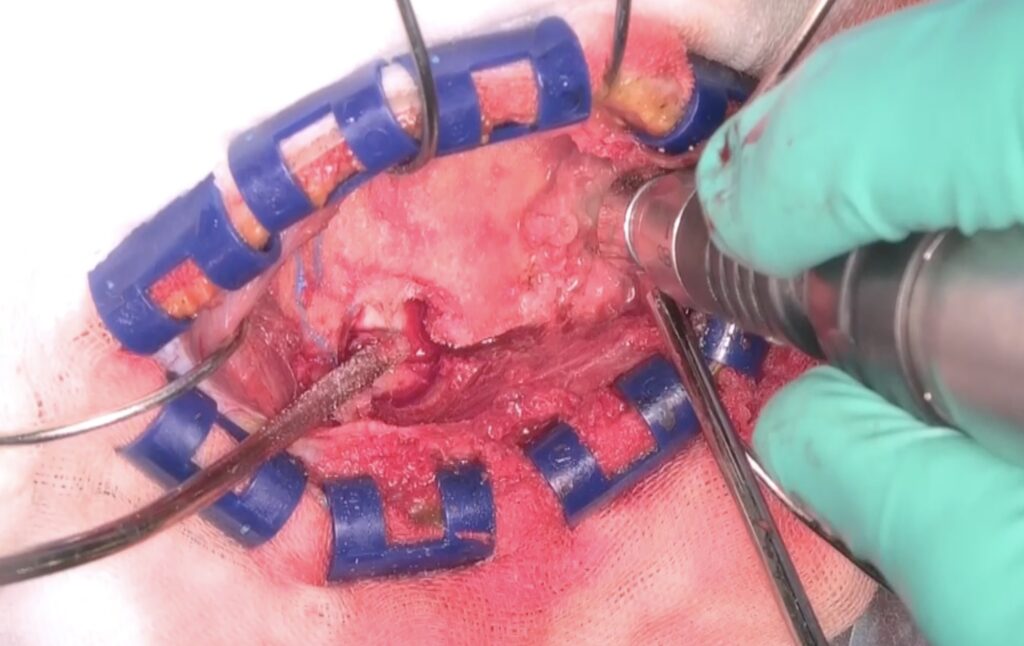

3cmx2cmの鍵穴開頭によるクリッピングを行いました。蝶形骨縁を十分にドリルしました。

硬膜切開を行い、シルビウス裂を開けると動脈瘤が容易に露出されました。